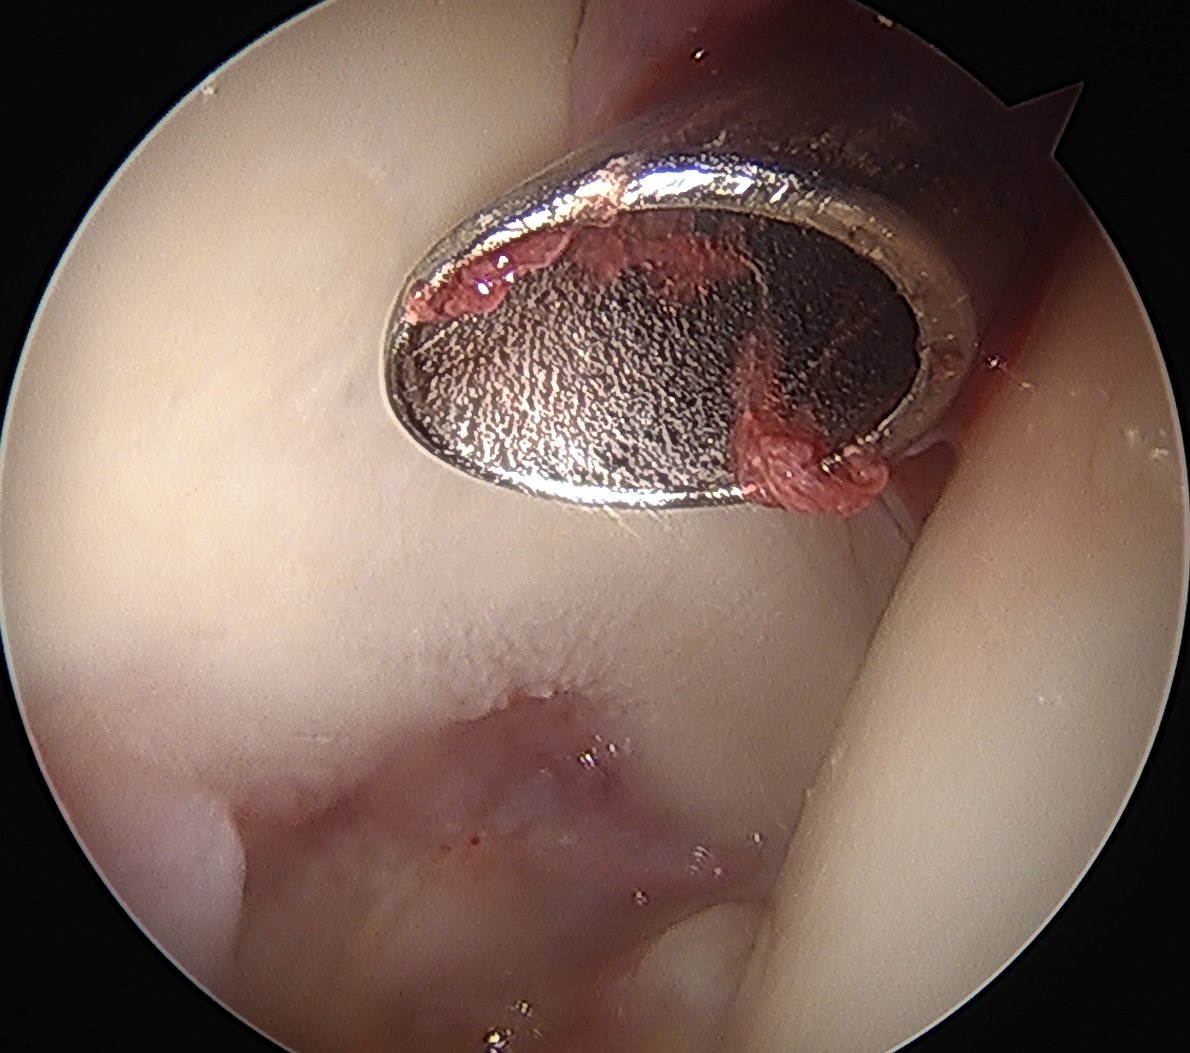

Acetabular rim trim / Acetabuloplasty

Pincer resection

Os acetabuli resection

Labral repair